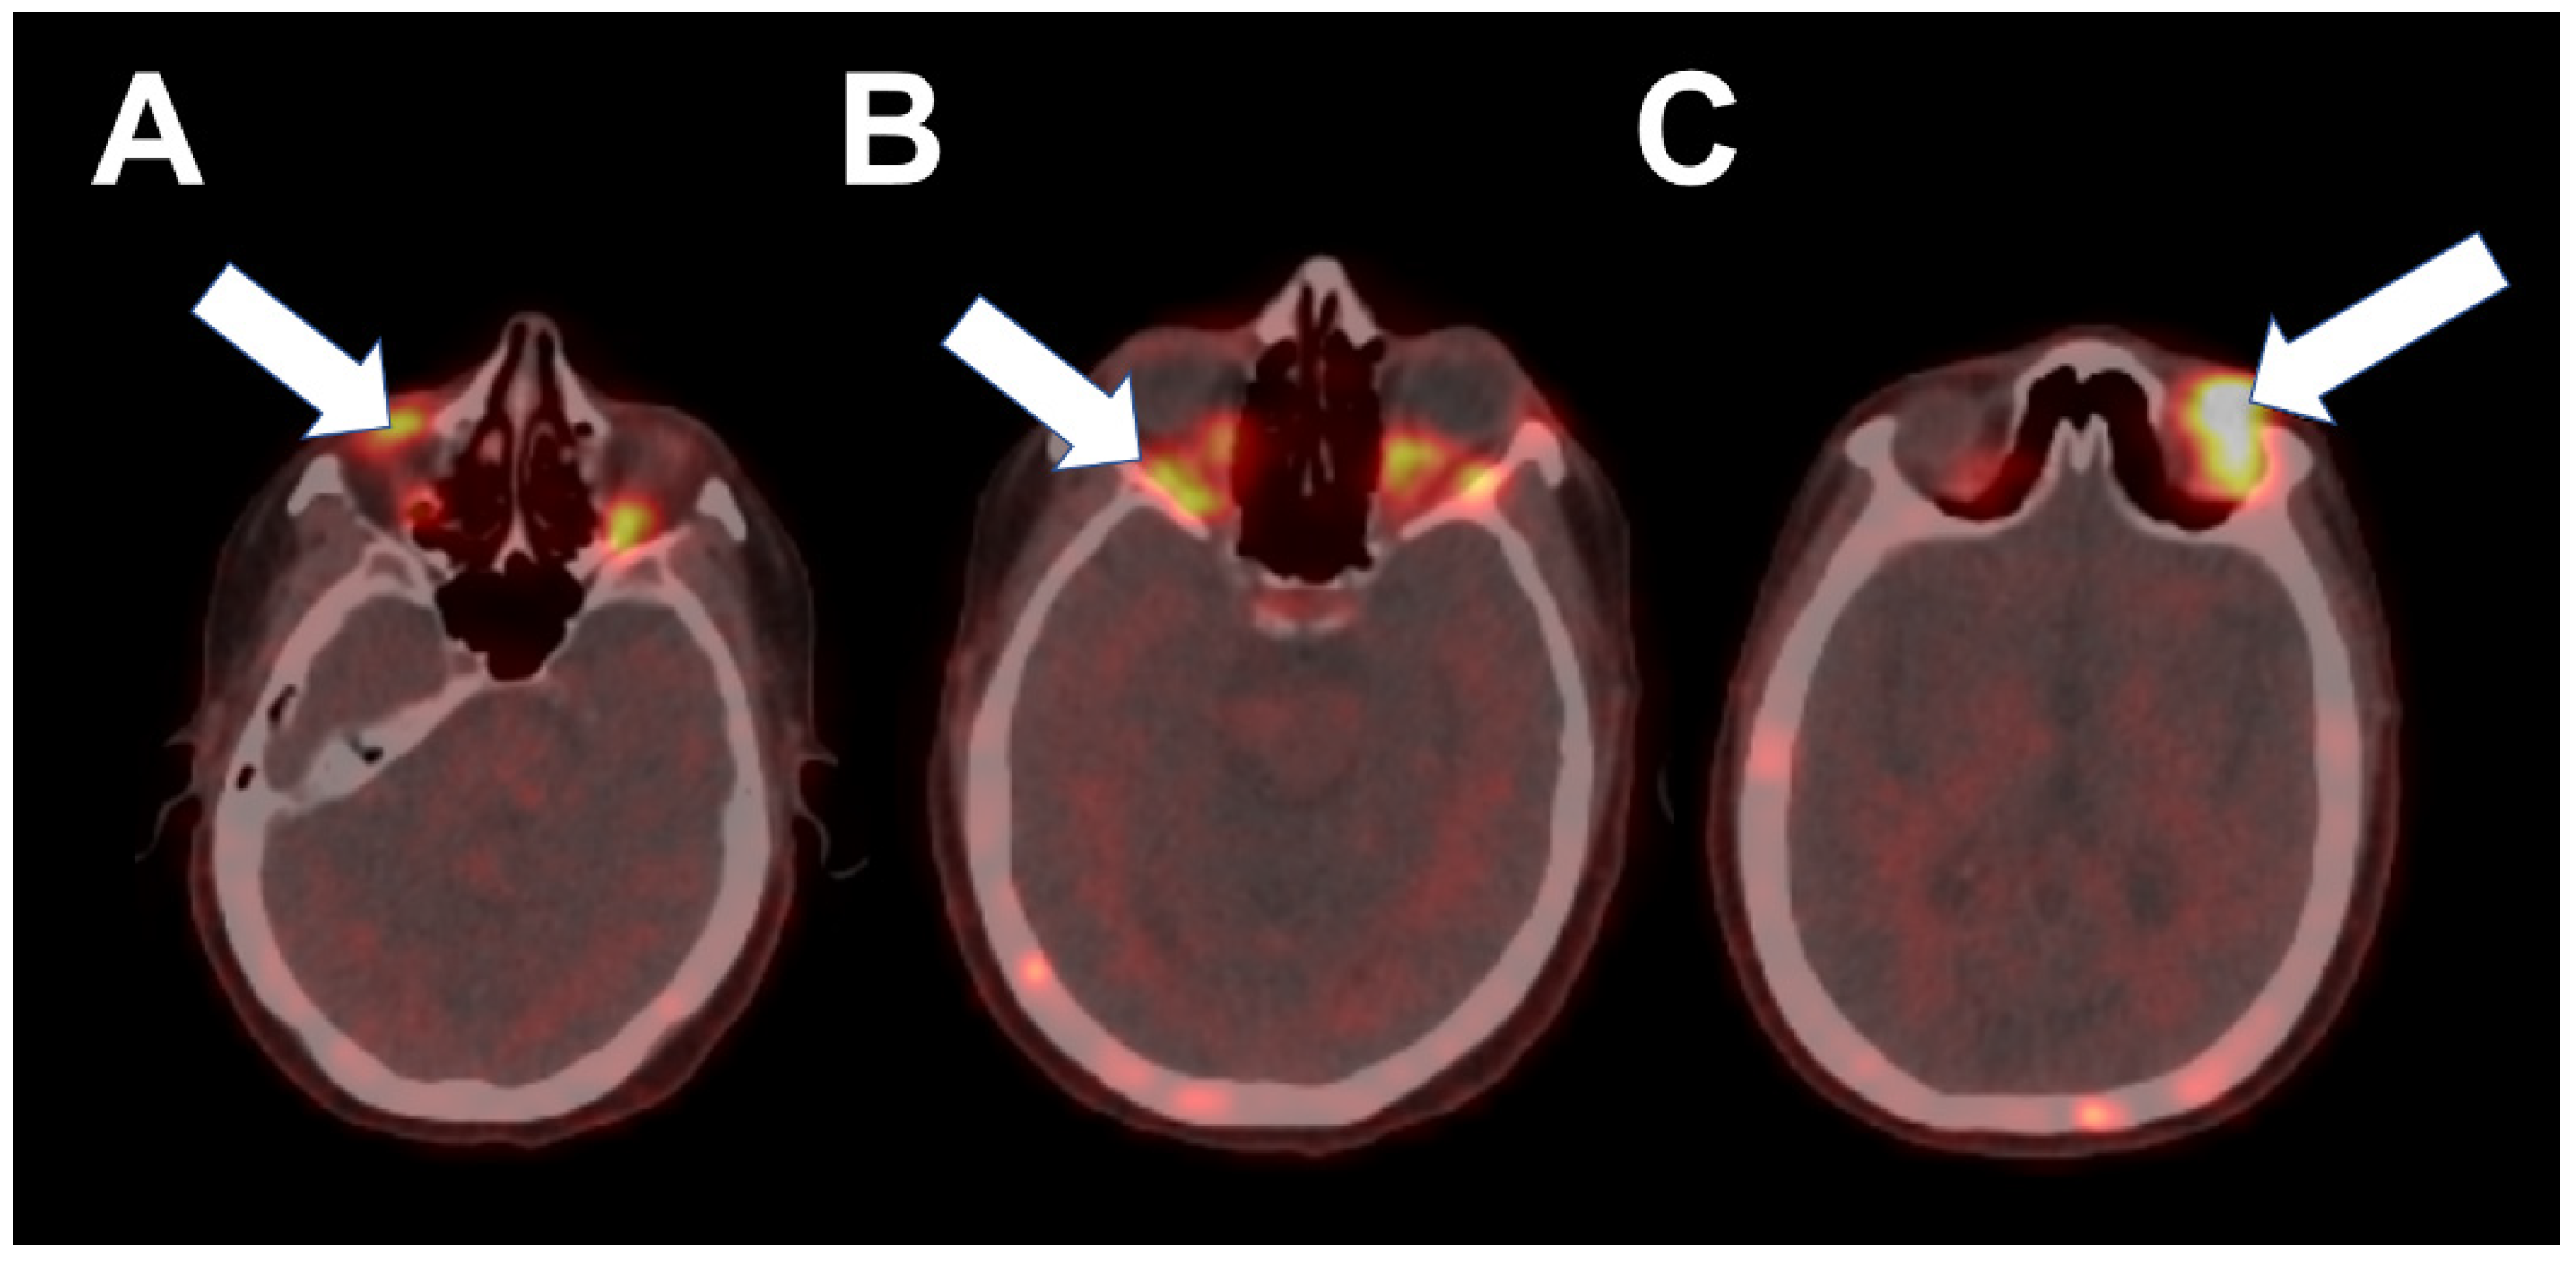

2. Case 1